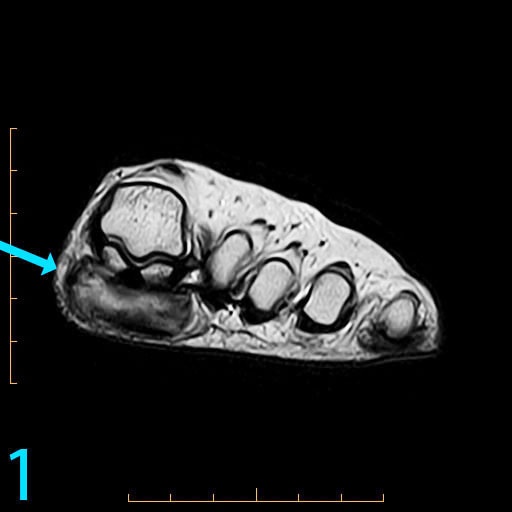

This 18-year-old female presents with a palpable soft tissue mass subjacent to the first metatarsophalangeal (MP) joint that she has noticed for 1-2 months. It is painful with shoes and ambulation, and you are evaluating her for a soft tissue tumor. What is the cause of her problem, and what pertinent negatives must you notice?

This patient has a so-called "pressure lesion" due to ambulation, with associated adventitial bursa/pseudobursa formation within. It is a chronic process. This is manifested as a large, ovoid mass-like structure within the subcutaneous soft tissues along the plantar aspect of the first MP joint and sesamoid bones (arrow). It is well-circumscribed and demonstrates a mildly lobulated configuration. There is peripheral signal hypointensity indicating a rim or rind of fibrosis, and there is intermediate to high T2 signal centrally, suggesting a component of complex fluid. The major differential diagnosis is fibroma of tendon sheath. This is a counterintuitive diagnosis as fibrous lesions are typically dark on all pulsing sequences. But, fluid signal from the tendon sheath may be found in this specific fibrous tumor. So, fibromas of tendon sheath are typically hyperintense centrally.

While the lobulation of the lesion medially is reminiscent of plantar fibromatosis, the constellation of findings remains most compatible with a giant pressure lesion. Fibromatosis (non-aggressive type) occurs more proximally in the middle aponeurotic cord of the plantar fascia. The findings are not suspicious of an aggressive neoplastic lesion (based on location and concentric shape), and you can also rule out MP joint capsulitis and Morton's neuroma because of location. You should always rule out plantar plate tear along the second MP joint on thin section sagittals if you have a large pressure lesion under the second metatarsal head. For more case review, visit MRI Online.